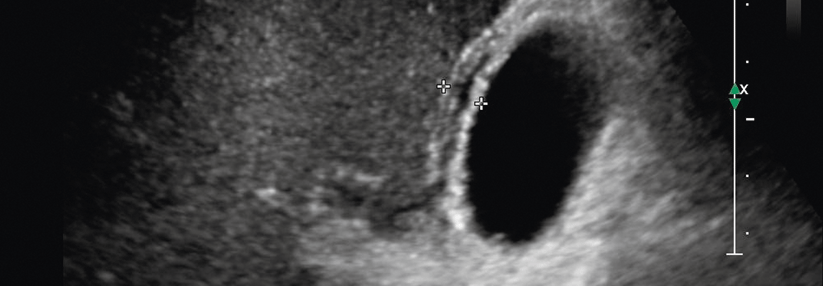

Am abdominalen Aortenaneurysma (AAA) erkranken vor allem Männer (4–8 % der über 65-Jährigen). Als weitere Risikofaktoren gelten Nikotinkonsum, Hypertonie und Hypercholesterinämie, aber auch eine positive Familienanamnese und Aneurysmen in anderen Körperregionen. Ein Großteil der Betroffenen hat keine Symptome (Stadium I), deshalb wird die brisante Gefäßveränderung meist zufällig im Ultraschall oder bei anderweitiger Röntgendiagnostik entdeckt, schreiben Matthias Trenner, Gefäßchirurg am Klinikum rechts der Isar der TU München, und seine Kollegen.

Im symptomatischen Stadium II klagen die Patienten über Rücken- und Bauchschmerzen, ggf. lässt sich…